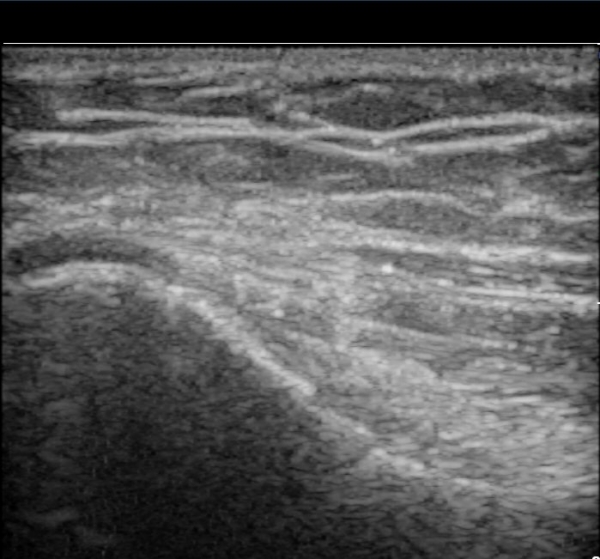

ÃÊÀ½ÆÄ °Ë»ç

³»»ó°ú Á¾´Ü¸é°Ë»ç¿¡¼­ ³»»ó°ú ±¼°ñ°Ç ºÎÂøºÎ¿¡ Àú¿¡ÄÚ º´º¯ÀÌ °üÂûµÈ´Ù. °Ç ½ÉºÎÀÇ

³»ÃøºÎÀδë´Â ƯÀÌ ¼Ò°ßÀ» º¸ÀÌÁö ¾Ê´Â´Ù(±×¸² 1, 2).